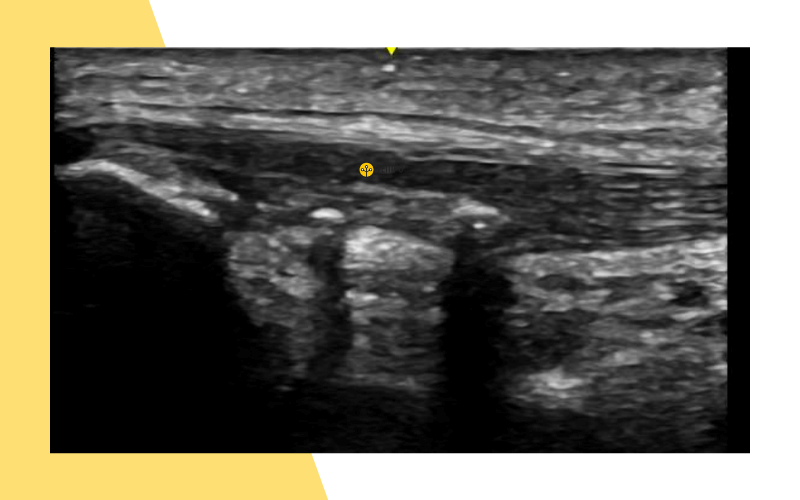

1. Esta imagen se corresponde con:

A. Rotura muscula aguda.

B. Hematoma encapsulado.

C. Variz venosa.

1. Respuesta correcta: B. Hematoma encapsulsado.

Porqué los rebordes están engrosados, irregulares y no tienen comunicación con el exterior del hematoma, y ante la presión no se colapsa.

2. ¿En qué vientre muscular se encuentra esta afectación?

A. Vaso interno.

B. Vaso externo.

C. Recto anterior.

2. Respuesta correcta: C. Recto anterior.